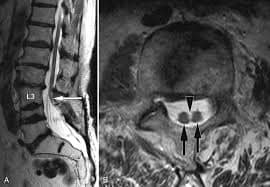

فقد تم اجراء عمليه جراحيه معقدة ونادره لطفل يبلغ من العمراسبوعين يعاني من تشوه خلقي مزدوج من فتق سُحائي وتشوه في العمود الفقري مع وجود نتوء عظمي يتسبب بـ نخاع شوكي منشق (مزدوج (

ولأول مرة في مستشفى الزرقاء الحكومي من قبل الدكتور فراس حداد / استشاري أول جراحة الدماغ والأعصاب، رئيس إختصاص جراحة الدماغ والأعصاب في الخدمات الطبية الملكية سابقاً الذي قام بإجراء العمليه، بمساعدة نخبة مميزة من الكادر الطبي على رأسهم الدكتور رأفت بواعبه مقيم جراحه الدماغ والاعصاب. كما شارك الكادر التمريضي وانجاح العملية وعلى راسهم الممرض مراد الزيود و الممرضة هبه المومني و الممرضة خوله ابوهاني جهودكم مشكوره بالاضافة الى أطباء قسم التخدير اطباء التخدير الدكتور أنس وفنية التخدير إيناس